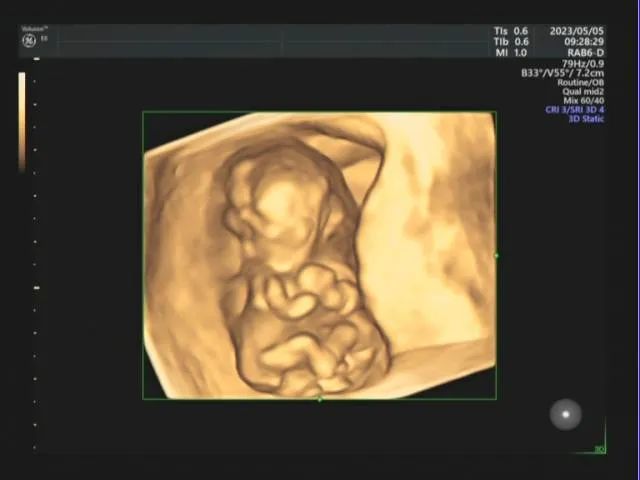

终于等到孕12周,这位孕妈妈来做早孕NT的超声检查。由超声科医生接诊,超声影像显示:两胎儿可见共同头颅结构,共同胸腔,腹腔,可见共同心脏,可见搏动,分别拥有自己各自的脊柱,上肢,下肢。超声提示:宫内双胎、活胎(联体双胎)。

联体双胎发生于胚胎发育的早期,当胚胎发育成形后超声即可发现此类畸形,通常联体双胎的类型不同,超声表现各不相同。产前超声应仔细观察胎儿内脏的形态 、位置 、数目,进行畸形分类。产前超声对本例联体双胎畸形诊断简单明了,易于发现确诊,随着产前超声的普及应用,此类畸形的发现变得简便可行。